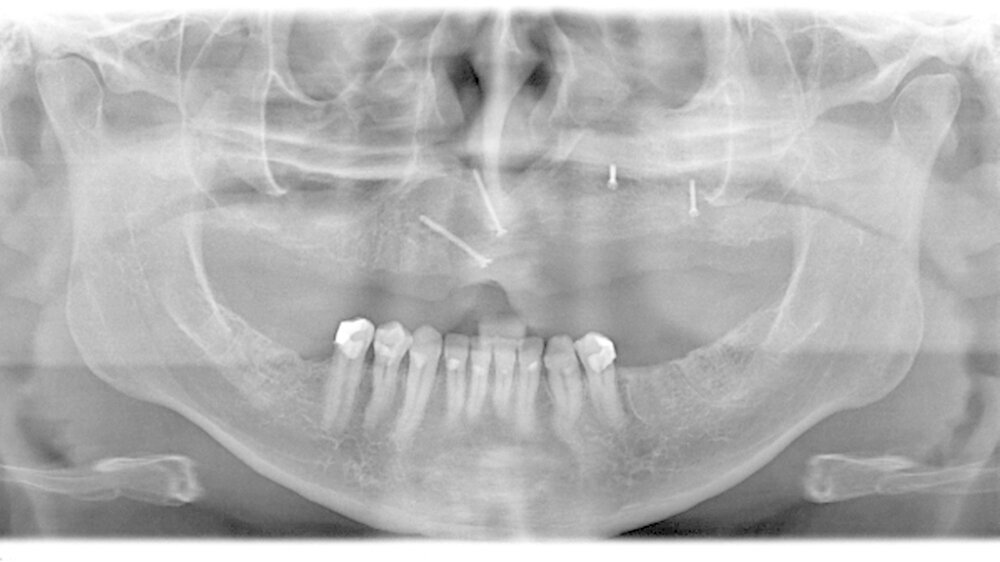

Bereits damals wurde vom Hauszahnarzt eine Entfernung der noch umschriebenen Raumforderung dringend empfohlen. Der Zahnfilm zeigte ein zystisches Geschehen in der Regio 24 und 25 (Abbildung 4). Zur aktuellen weiteren präoperativen Diagnostik wurde eine Computertomografie angefertigt. In den coronalen Schnitten ist die die Mittellinien überschreitende Raumforderung bis zum knöchernen Nasenboden unter Einbezug der linken Kieferhöhle deutlich zu sehen (Abbildung 5a). Man erkennt insbesondere in den sagittalen Schnitten, dass die Raumforderung über zwei Drittel der linken Kieferhöhle beansprucht (Abbildung 5b).